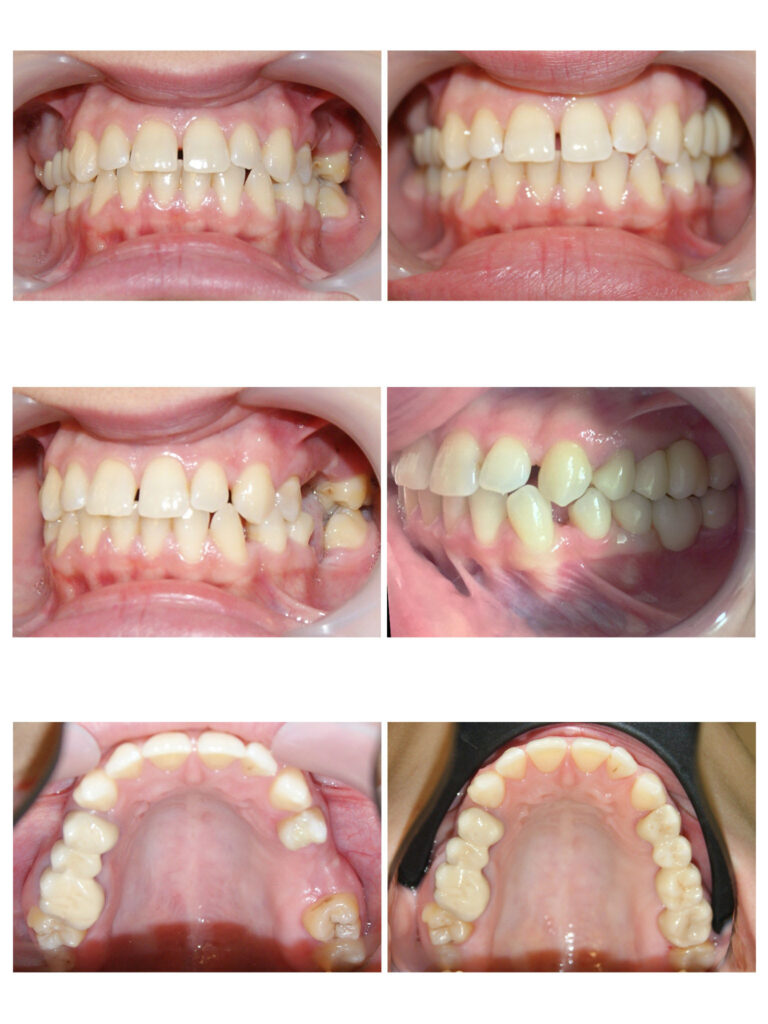

Persistența dinților de lapte peste timpul lor normal de exfoliere determină înghesuirea dinților definitivi. Aparatele dentare fixe sunt instrumentele perfecte pentru alinierea armonioasă a dinților